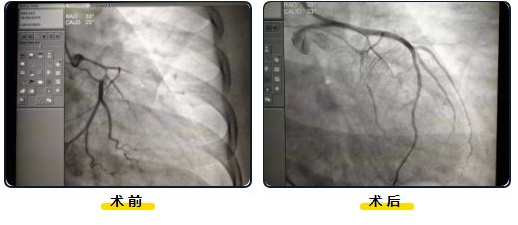

结合患者症状、急诊立即行心电图等检查,诊断为"急性广泛前壁心肌梗死",急诊科医生立即电话通知心内科主任彭描宇,彭描宇接到消息,刻不容缓,立马放弃周末休息从家中奔赴医院,他深知此刻时间就是生命,一秒都不能拖延,几分钟就赶到科室,考虑到当时患者生命体征不稳定,呼吸困难,随时有生命危险,他立即为患者开通绿色通道。启动急诊PCI手术(急诊经皮冠状动脉介入手术)流程。一方面立马通知手术人员到位,介入室准备到位,另一方面积极与家属沟通、告知患者病情的危险性及解决方法,签署手术同意书后,迅速将患者送入介入室,为其实施了急诊PCI手术,造影显示左主干及前降支90%狭窄,远端闭塞,术中患者血压极不稳定,出现急性肺水肿呼吸困难,多次吸出粉红色泡沫样痰,反复发生室速、室颤。手术团队处乱不惊,台上多次电复律除颤后成功转复,紧急开通血管前降支,保障了手术的顺利进行。

手术现场

经过约1小时紧张有序、争分夺秒的手术操作,以彭描宇主任为主的心内科手术团队成功将患者冠脉打通,在患者左主干及前降支植入两枚支架,支撑起闭塞的血管打通了生命线,患者胸痛症状马上有了明显改善。对照术前术后两张造影片,参加抢救的工作人员才长长地舒了一口气,紧张有序的抢救工作也告一段落了,他们疲惫的脸庞上终于露出了笑容。